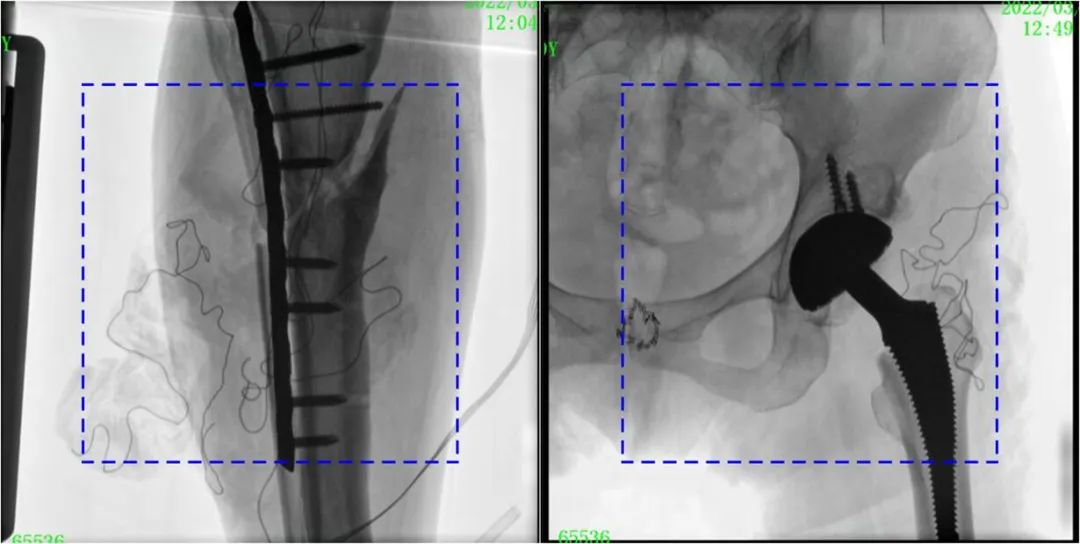

C形臂輔助手術過程

術中使用普愛醫療大平板一體式C形臂進行透視,判斷骨折情況及克氏針、髓內釘等金屬植入物的位置,進行調整。C形臂準確的術中定位,大大縮短了手術的時間,減輕了患者的痛苦,輔助手術順利完成。

在進行髓內釘內固定術時,醫生需要同時觀察到入釘點和骨折部位的情況,普愛醫療大平板一體式C形臂采用30CM×30CM的平板探測器,能夠呈現更廣闊的成像面積,滿足大部分長骨髓內釘內固定術的攝片需求。

術中定位準確、出血量少,術后影像顯示股骨移位糾正,恢復良好力線,手術效果良好。

PLX119C臨床圖像與傳統圖像對比

注:藍色虛線內為傳統21CM×21CM平板的成像區域。